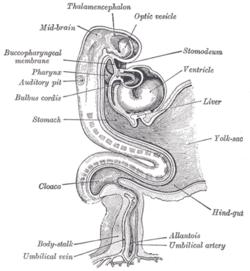

Human embryo about fifteen days old. Brain and heart represented from right side. Digestive tube and yolk sac in median section. (Optic vesicle labeled at center top.) | |